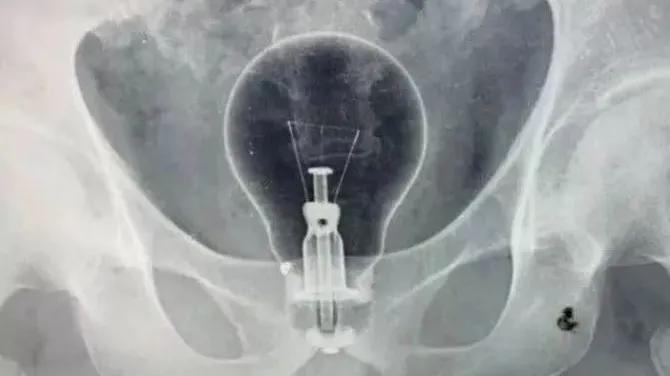

假设你是一位肛肠科医生 完全可以组织一次“直肠异物大赏”

你究竟能认出几种

塞入直肠里的异物“应有尽有”

灯泡、茄子、花露水瓶、……

西南医科大学附属中医医院肛肠科主任李五生教授说:直肠异物是直肠里出现除了粪便以外的其他东西,比如灯泡、按摩棒、玻璃药瓶、陀螺、蜡烛、圆柱形金属瓶等等,甚至常见的蔬菜和长条状的物体,比如黄瓜、火腿肠、茄子、苦瓜、黄鳝、泥鳅……